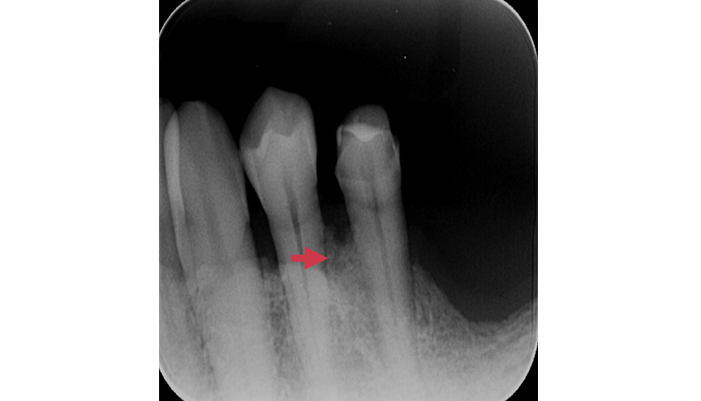

症例2

治療前

治療後

| 主訴 | 上の前歯がよく腫れる |

|---|---|

| 治療期間 | 1~2ヶ月 |

| 治療費 | ¥77,000(税込) |

| 治療内容 | 歯周再生療法にて、歯周病で失った骨を再生しました。 |

| 治療のリスク | 100%成功するものではなく、適応出来ないケースもあります。 |